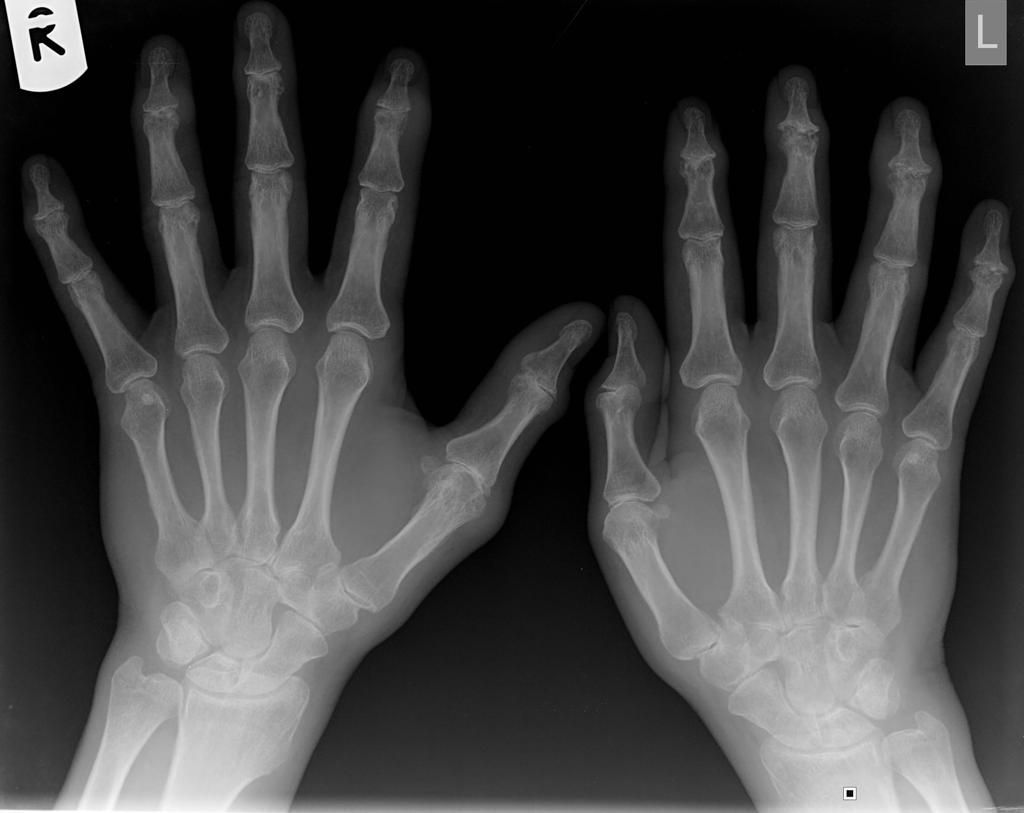

Pencil-in-Cup deformity may be demonstrated in individuals with psoriatic arthritis. This deformity is referred to as 'Pencil-in-Cup' since one bone is eroded to become sharp and pointy which resides in a cup-shaped bone. Reference: https://www.verywellhealth.com/pencil-in-cup-deformity-5193284#:~:text=The%20term%20%E2%80%9Cpencil%2Din%2Dcup%E2%80%9D%20describes%20what%20is,and%20sharpened%20like%20a%20pencil. Image via: https://www.wikidoc.org/index.php/Psoriatic_arthritis_x_ray